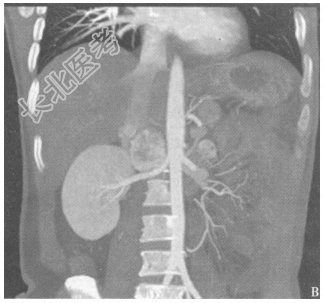

- 简答题3、患者的腹部+盆腔CT检查结果见图4、图5。患者目前可能的诊断是